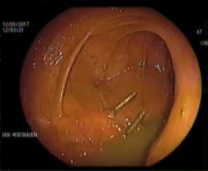

病例三 77岁女性复发性胃肠道出血,需要多次输血并入住ICU。(d)栓塞后无外渗。箭头指向栓塞部位。